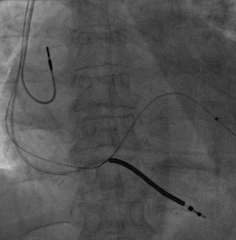

选择哪根靶静脉?

选择后侧静脉,Runthough导丝顺利通过并与心中静脉交通回到右心房,但左室4298电极无法通过狭窄处。

因4298外径在5.3F,故选用Maverick2.0X15mm预扩球囊在狭窄处给予充分扩张

扩张后电极仍无法通过

尝试心中静脉,但血管扭曲,导丝进入困难

尝试侧静脉,但远端过于狭窄,电极无法完全进入分支,测试结果不理想,只能放弃该血管

再次尝试后侧静脉,改用Sprinter Legend2.5X15mm预扩球囊扩张,可见明显腊肠样狭窄,给予28atm时方可见完全扩张

电极仍然无法通过,造影发现狭窄依然存在

尝试鞘中鞘试图通过狭窄处,但电极仍然无法通过

尝试Quantum Maverick3.0X12mm后扩球囊进行扩张

电极依然无法通过狭窄处,放弃手术?